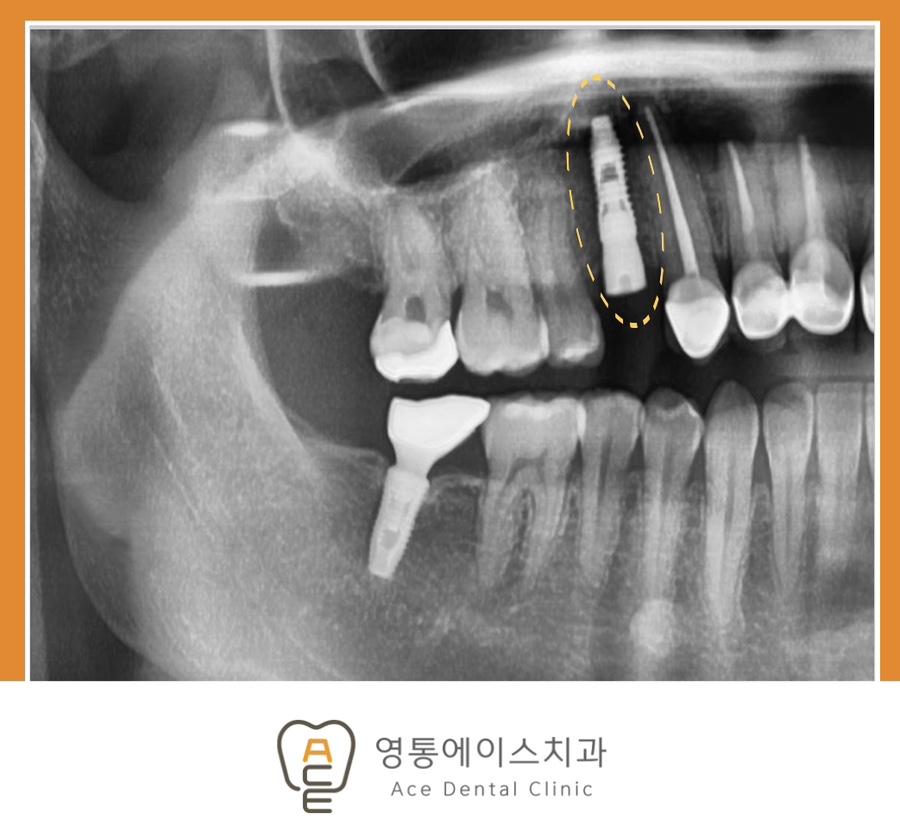

치료 후 사진 / 2026.01.06

결론부터 말씀드리면, 특별한 사유가 없다면 가능한 한 빠르게 치료를 시작하는 것이 좋습니다. 치아가 빠진 자리는 시간이 지날수록 잇몸뼈가 점점 흡수되기 때문입니다. 이 과정이 진행되면 임플란트를 식립할 수 있는 뼈의 양이 부족해져 추가적인 뼈이식이 필요할 수 있고, 치료 기간과 비용도 함께 증가할 수 있습니다.

특히 망포역임플란트를 고려하시는 경우라면, 상실 직후 상태를 유지하는 것이 치료 결과에 긍정적인 영향을 주는 경우가 많습니다. 잇몸뼈가 충분히 유지된 상태에서는 보다 안정적인 식립이 가능하며, 회복 속도 또한 비교적 원활한 편입니다.

임플란트 치료 과정은 먼저 정밀 진단을 통해 잇몸 상태와 뼈의 양을 확인하는 것에서 시작됩니다. 이후 개인의 구강 상태에 맞는 계획을 수립하고, 인공치근을 식립한 뒤 일정 기간 유착 과정을 거치게 됩니다. 마지막으로 보철물을 연결하여 자연치와 유사한 기능을 회복하게 됩니다.